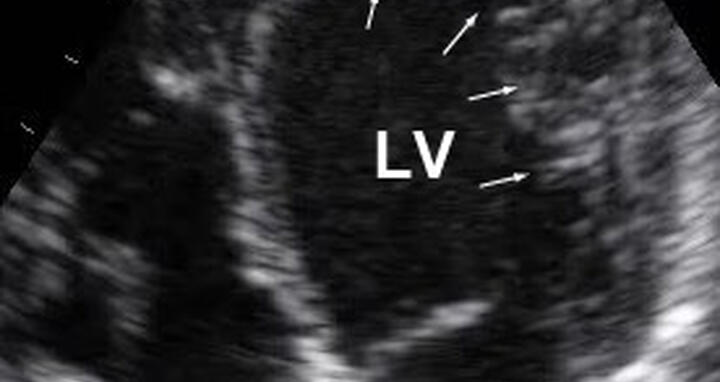

Beim gesunden Herz sind die linke (rechts oben – linker Ventrikel, LV) und die rechte Herzkammer (links oben) sowie ihre Vorhöfe von kompaktem Muskelgewebe umgeben. (Aufnahme: Sabine Klaassen/​Copyright: MDC)